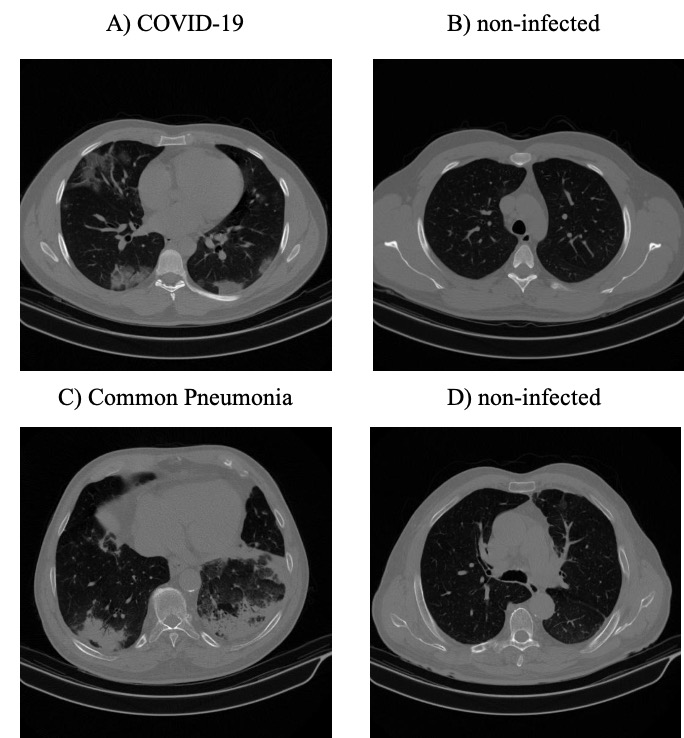

Figure 1: A, B: Infected and non-infected sample slices in a COVID-19 case; C, D: Infected and non-infected sample slices in a non-COVID Pneumonia case.

This research work is performed based on the policy certification number 300133943001339430013394 of Ethical acceptability for secondary use of medical data approved by Concordia University. The dataset used in this study, referred to as the “COVID-CT-MD” (Afshar et al., 2020a), contains volumetric chest CT scans of 171 patients positive for COVID-19 infection, 60 patients with community acquired pneumonia, and 76 normal patients acquired from April 2018 to May 2020. The average age of patients is 50±16plus-or-minus501650\pm 16 including 183 men and 124 women. Diagnosis of COVID-19 infection is based on positive real-time reverse transcription polymerase chain reaction (rRT-PCR) test results, clinical parameters, and CT scan manifestations by a thoracic radiologist, with 20 years of experience in thoracic imaging. Community acquired pneumonia and normal cases were included from another study and the diagnosis was confirmed using clinical parameters, and CT scans. A subset of 55 COVID-19, and 25 community acquired pneumonia cases were analyzed by the radiologist to identify and label slices with evidence of infection as shown in Figure 1. This labeling process focuses more on distinctive manifestations rather than slices with minimal findings. The labeled subset of the data contains 4,962 number of slices demonstrating infection and 18,447 number of slices without infection. The data is then used to train and validate the first stage of our proposed COVID-FACT model for extracting slices demonstrating infection from a volumetric CT data to be used in the second classification stage. We divided this subset into three separate components for training, validation, and testing. 60% of the labeled data is used for training, 10% for validation, and 30% for the test. The unlabeled subset is divided with the same proportion and used along with the labeled data to develop the second stage of the COVID-FACT model and evaluate the overall method.